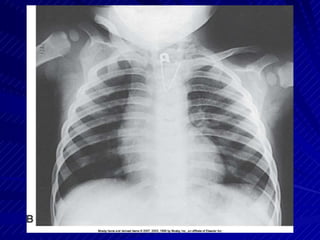

ChestChest

Supine position used if generalgeneral surveysurveySupine position used if

Trauma AP ChestTrauma AP Chest

Ensure chin extended out ofof anatomyanatomy ofofEnsure chin extended out

interest

CR directed perpendicular to center of

CR directed perpendicular to center IRof IR

– look forlook for lightlight field slightlyfield slightly above shoulders andabove shoulders and

on sides of chest, CW or LWLWon sides of chest, CW or

Exposure made upon second fullExposure made upon second full

inhalation, ifif possiblepossibleinhalation,

Image demonstrates lung fields in theirin theirImage demonstrates lung fields

entiretyentirety

– MinimalMinimal rotation and distortion presentrotation and distortion present